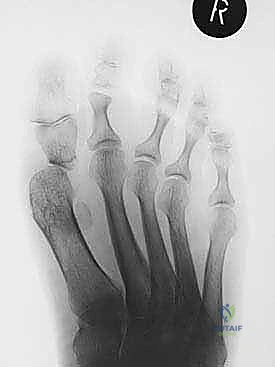

- التصوير بالأشعة السينية (X-rays): صور في وضعية الوقوف (تحمل الوزن) من زوايا متعددة لقياس زوايا التشوه بدقة وحساب مقدار الطول المفقود.

- الأشعة: يتم إجراء أول صورة أشعة سينية للمتابعة للتأكد من ثبات المسامير وبدء عملية الالتئام.

- إذا أظهرت الأشعة السينية علامات قوية لاندماج الطعم العظمي، يسمح د. هطيف بالتحميل التدريجي لوزن الجسم بالكامل أثناء ارتداء الحذاء الطبي الصلب.